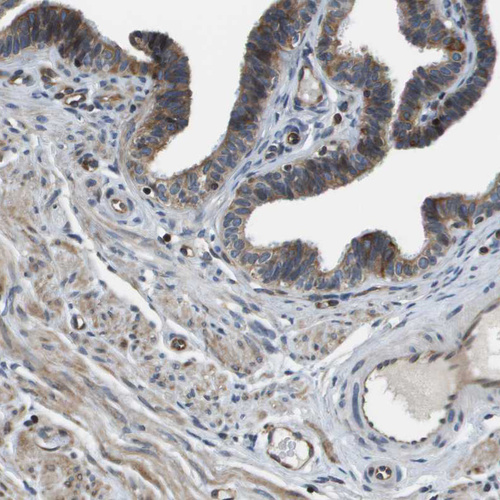

Immunohistochemical staining of human fallopian tube shows moderate cytoplasmic positivity in glandular cells and endothelial cells.